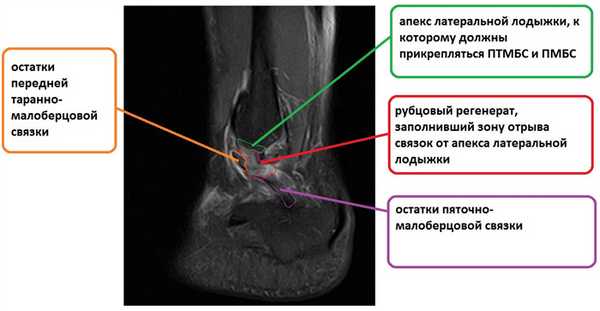

Ниже представлены срезы МРТ в которых наглядно показано расположение повреждённых связочных структур.

На этом этапе пациентка лечилась по стандартному сценарию «растяжение голеностопа». Носила ортез, мазала голеностоп вольтареном и лиотоном, разгружала его при помощи трости. Но в связи с длительно сохраняющимся болевым синдромом было выполнено МРТ, при котором диагностирован застарелый разрыв передней таранно-малоберцовой связки, пяточно-малоберцовой связки правого голеностопного сустава, контузионное повреждение латеральных отделов таранной кости.

После подтверждения нестабильности и устранения разрастаний синовиальной и рубцовой ткани переходим к этапу забора аутотрансплантата и его подготовки к последующей трансплантации. У транспланатата 2 плеча, сложенная вдвое часть погружается в канал малоберцовой кости, а «рукава» фиксируются в каналах таранной и пяточной кости соответсвенно в месте прикрепления передней таранно-малоберцовой и пяточно-малоберцовой связок.

После подготовки транспланата выполняется продольный доступ в проекции апекса латеральной лодыжки, из которого выделяется передняя таранно-малоберцовая связка, чаще всего она бывает частично замещена рубцом в зоне прикрепления к малоберцовой кости, её желательно сохранить, прошить, и потом произвести аугментацию пластики её остатками, что будет способствовать скорейшему восстановлению проприорецепции, и вообще сделает такое восстановление возможным. Первый этап - проводим пуговичный фиксатор (в нашем случае Tight rope Arthrex) через канал в малоберцовой кости. Канал делается при помощи 2 канюлированных свёрел, 4 мм сверлом делается сквозной канал, для того чтобы через него могла пройти пуговица. Второе сверло соответсвует по диаметру сложенному вдвое транспланатау, обычно это 5 или 6 мм и этот канал заканчивается слепо на глубине 2 см, для жёсткой фиксации трансплантата после затягивания нитей на пуговчатом фиксаторе.

На этой фотографии под остатками ПТМБС виден трансплантат. Культя собственного сухожилия подшивается поверх него к надкостнице малоберцовой кости.